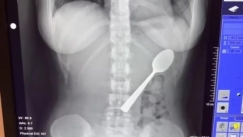

VIRAL 24/08/2025 - 21:25 Τανζανία: Έβγαζε πύον από τις θηλές του και οι γιατροί ανακάλυψαν μαχαίρι στο στήθος του επί 8 χρόνια (vid)